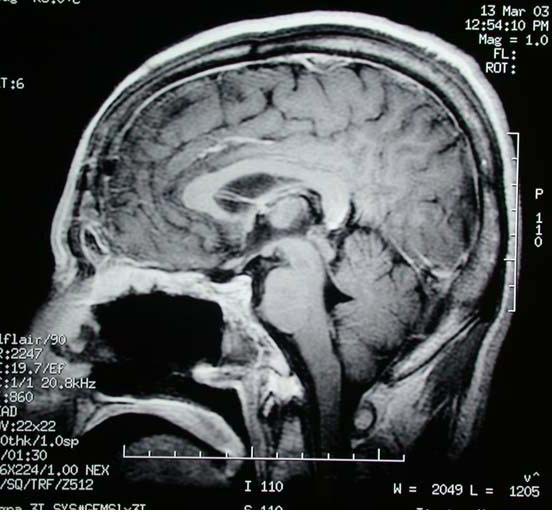

术前